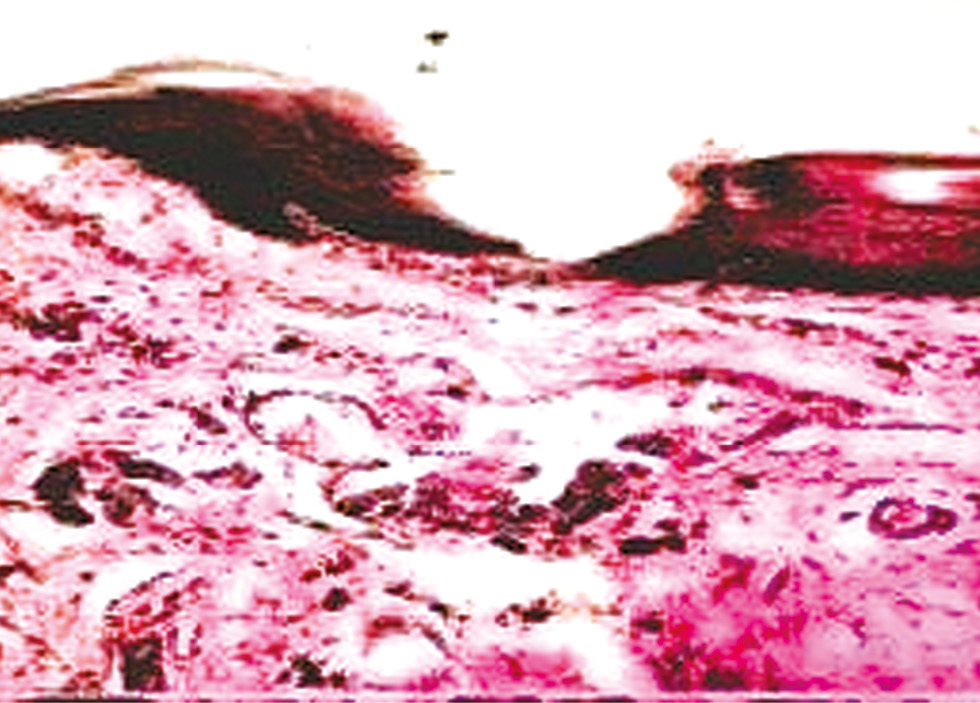

Histomorphologic analysis of oral mucosal tissues in patients with Ftorax acrylic resin dentures coated with Gluma Comfort Bond adhesive revealed flattened epithelial cells across relatively large areas, thinning of the keratinized layer, and positive structural changes in the basal membrane, including decreased stromal edema, fewer mast cells, and increased minor salivary gland elements (see Fig. 7). However, the positive morphologic changes were more pronounced in TG-2a and TG-2b than in RG-2.

Fig. 7. Submucosal section beneath dentures fabricated from Ftorax acrylic resin. Hematoxylin and eosin stain; ×100.